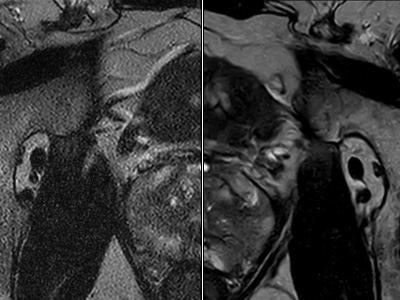

Philips SmartSpeed, une technologie basée sur l'IA capable d'augmenter la résolution sans prolonger le temps d'acquisition.